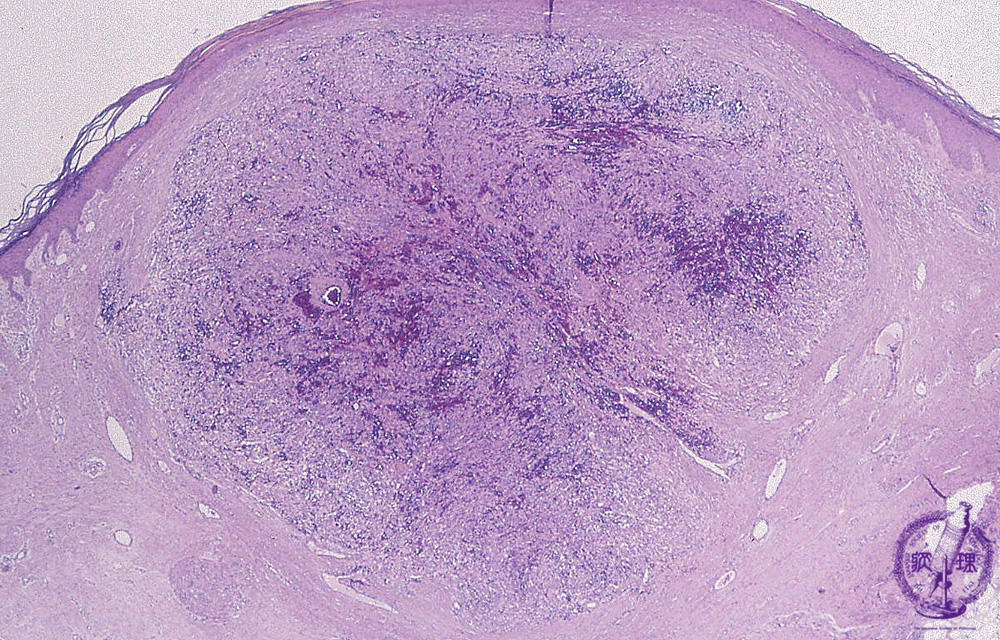

Microscopic findings (H.E. low power view): Kaposi sarcoma is occasionally associated with acquired immunodeficiency syndrome (AIDS). A relatively well circumscribedmass with a proliferation of spindle cells in bundles.